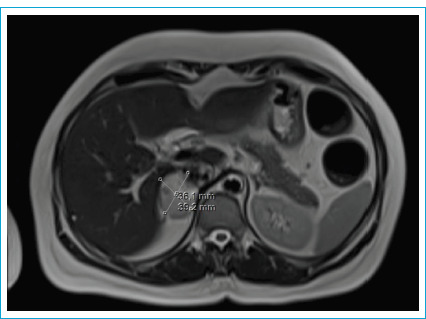

嗜铬细胞瘤是一种起源于肾上腺的罕见肿瘤,以分泌儿茶酚胺为特征。由于高血压危象与儿茶酚胺释放相关,嗜铬细胞瘤患者的手术治疗是有风险的。在这个病例报告,腹腔镜阑尾切除术急性阑尾炎患者谁有嗜铬细胞瘤将提出。女性,49岁,腹痛。体格检查显示右下腹有防守和反弹。患者在调查中有白细胞增多,腹部计算机断层扫描显示急性阑尾炎和5厘米右肾上腺肿块的迹象。六个月前内分泌科的腹部磁共振成像显示右肾上腺有一个39x32毫米的肿块,尿儿茶酚胺水平升高。据了解,该病人在此期间没有参加后续预约。患者接受内分泌科会诊,并进行了紧急腹腔镜阑尾切除术。患者于术后第2天出院,未出现任何并发症。患者转至内分泌科,开始进行嗜铬细胞瘤手术的术前准备。在紧急情况下,诊断为嗜铬细胞瘤的患者可以在适当的术前准备下进行紧急手术。

Pheochromocytoma is a rare tumor originating from the adrenal gland, characterized by the secretion of catecholamines. Due to the risk of hypertensive crises associated with catecholamine release, surgical procedures in pheochromocytoma patients are risky. In this case report, laparoscopic appendectomy for acute appendicitis in a patient who has pheochromocytoma will be presented. A 49-year-old female patient presented with abdominal pain. Physical examination showed guarding and rebound in the right lower quadrant. The patient, who had leukocytosis in the investigations, showed signs of acute appendicitis and a 5 cm right adrenal mass on the abdominal computed tomography. A previous abdominal magnetic resonance imaging by the endocrinology department six months ago revealed a 39x32 mm mass in the right adrenal gland and elevated urinary catecholamine levels. It was learned that the patient had not attended follow-up appointments during this period. The patient was consulted by endocrinology and an emergency laparoscopic appendectomy was performed. The patient, discharged on the 2nd day after surgery, did not experience any complications. The patient was referred to endocrinology, and preoperative preparations for pheochromocytoma surgery were initiated. In cases of emergency in patients diagnosed with pheochromocytoma emergency surgery can be performed with appropriate preoperative preparation.